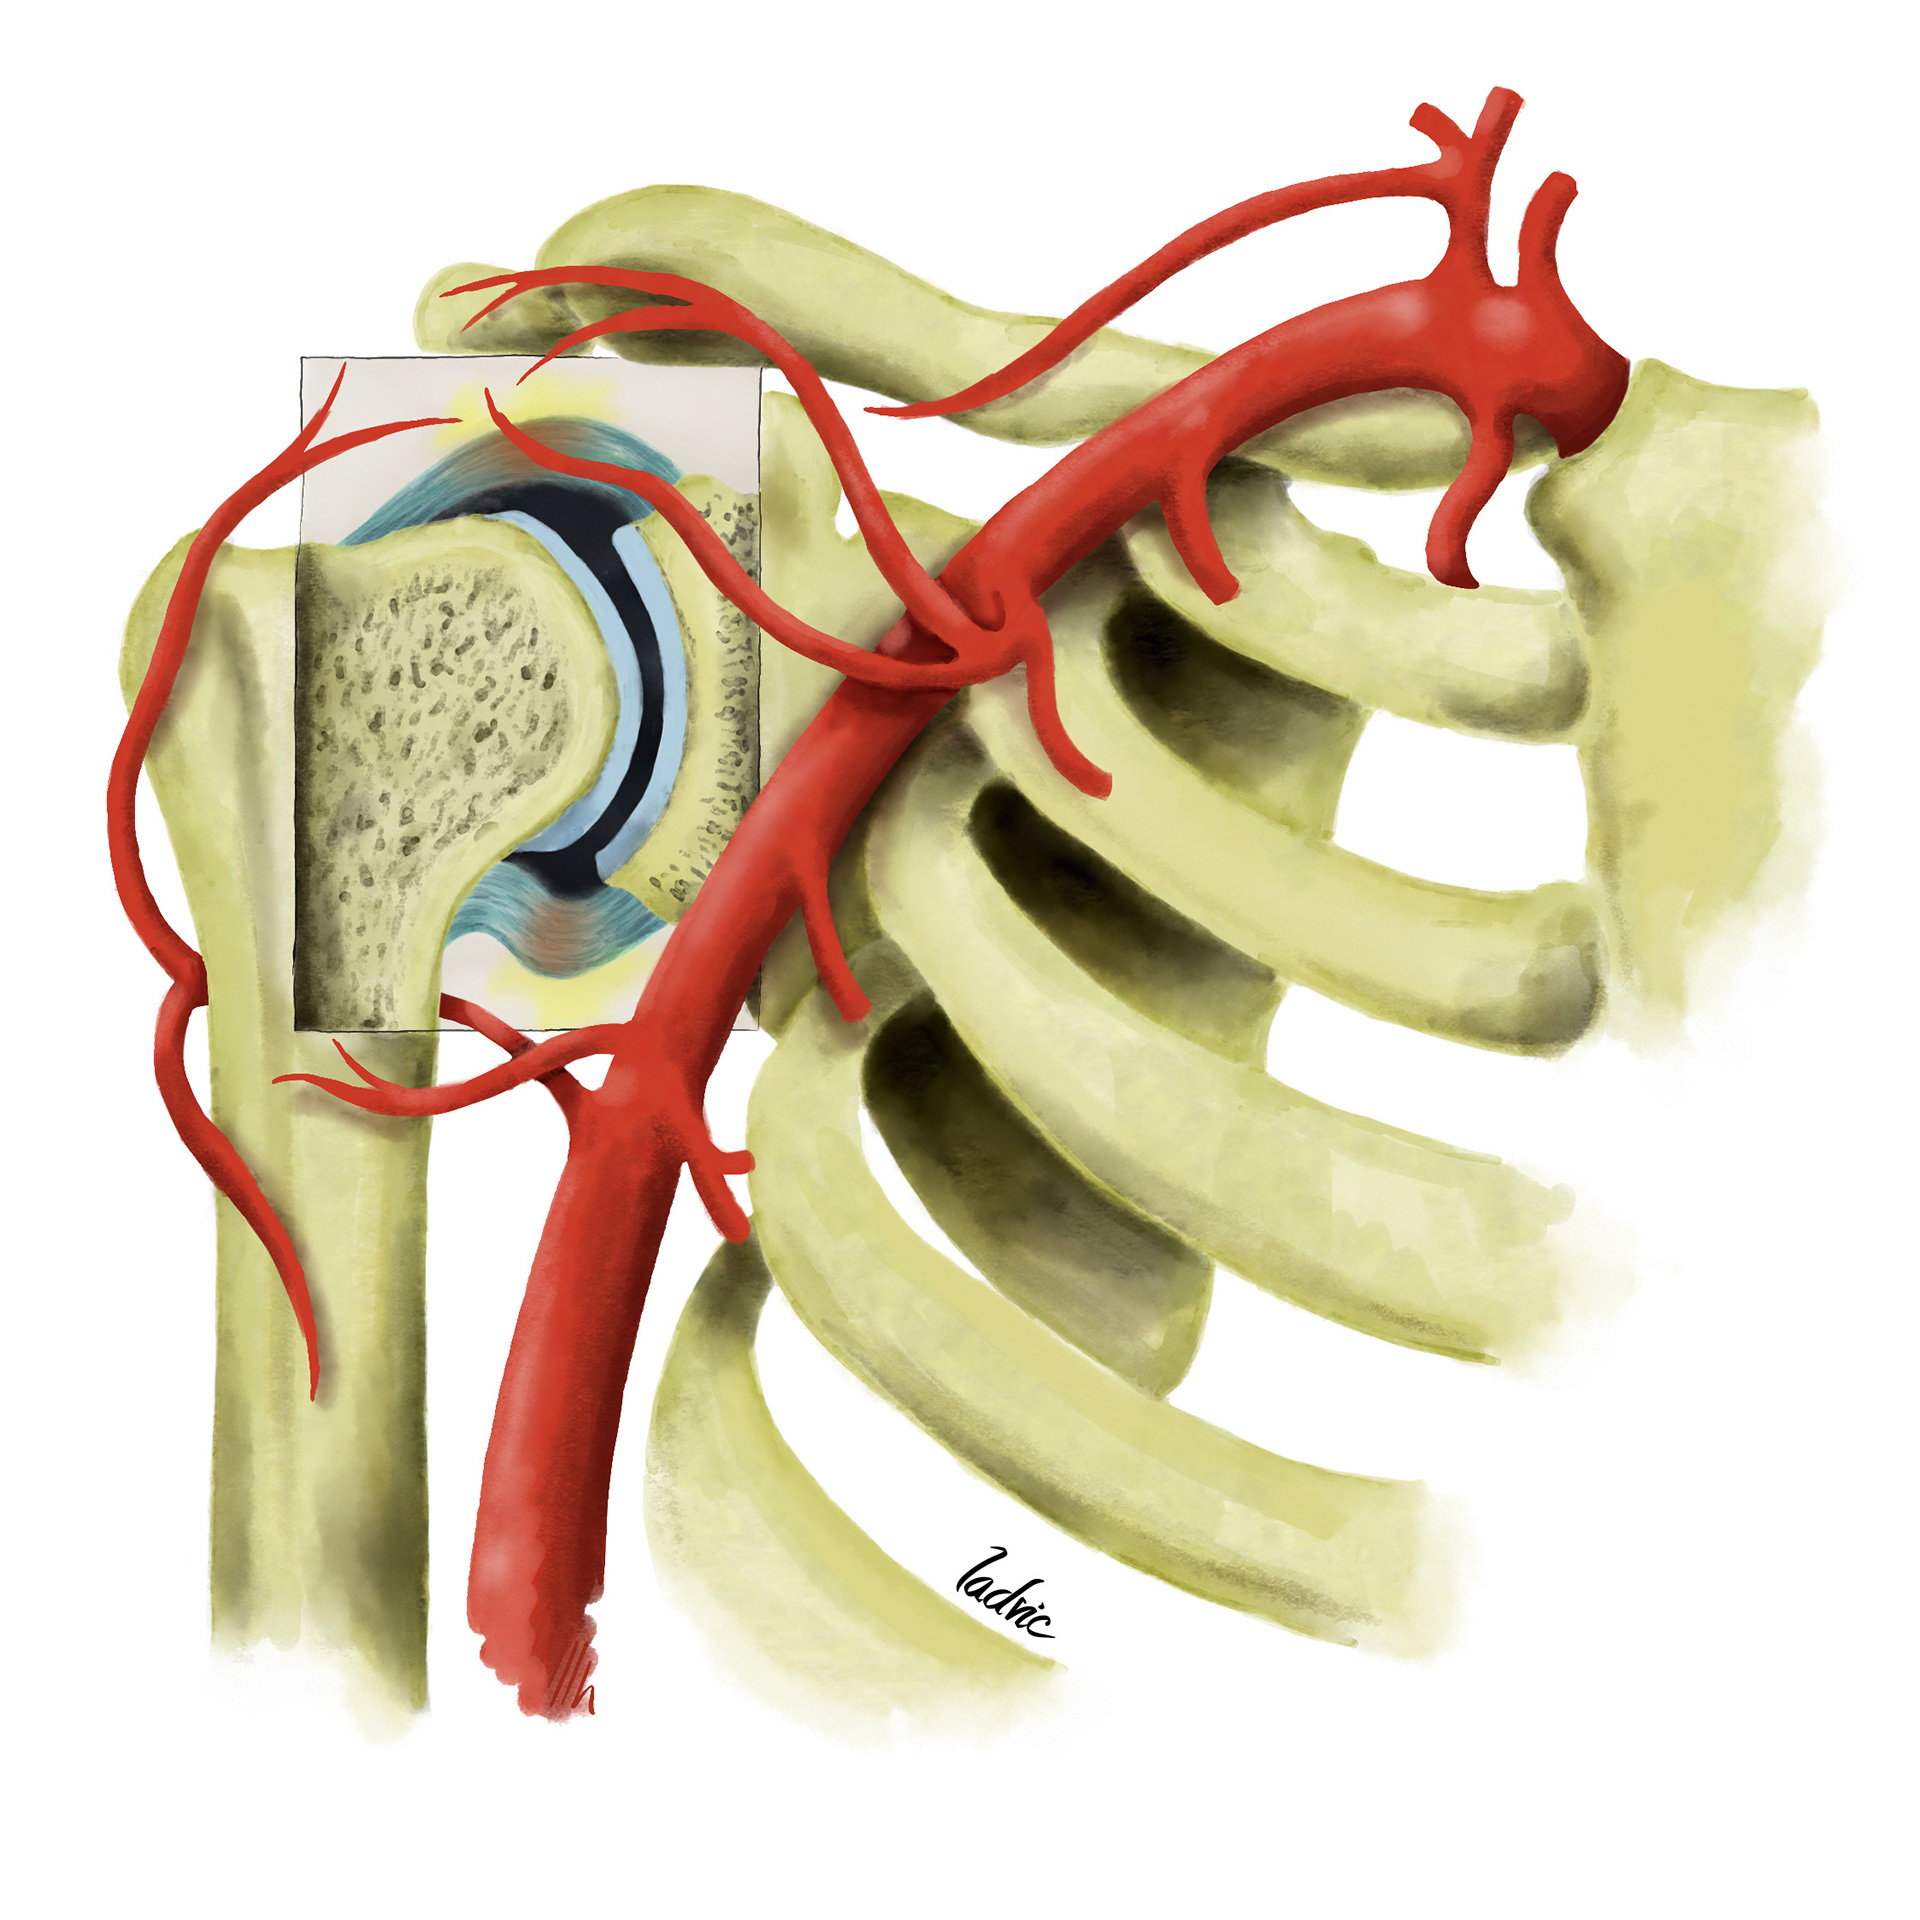

Illustration to show the vascularitation of the shoulder and diferent anatomical variants. It was made for a presentation of endovascular treatment of shoulder capsulitis.

I draw the anatomical variants over the same first draw but decided to desaturate the main artery so the variant could stand out.

I draw the anatomical variants over the same first draw but decided to desaturate the main artery so the variant could stand out.